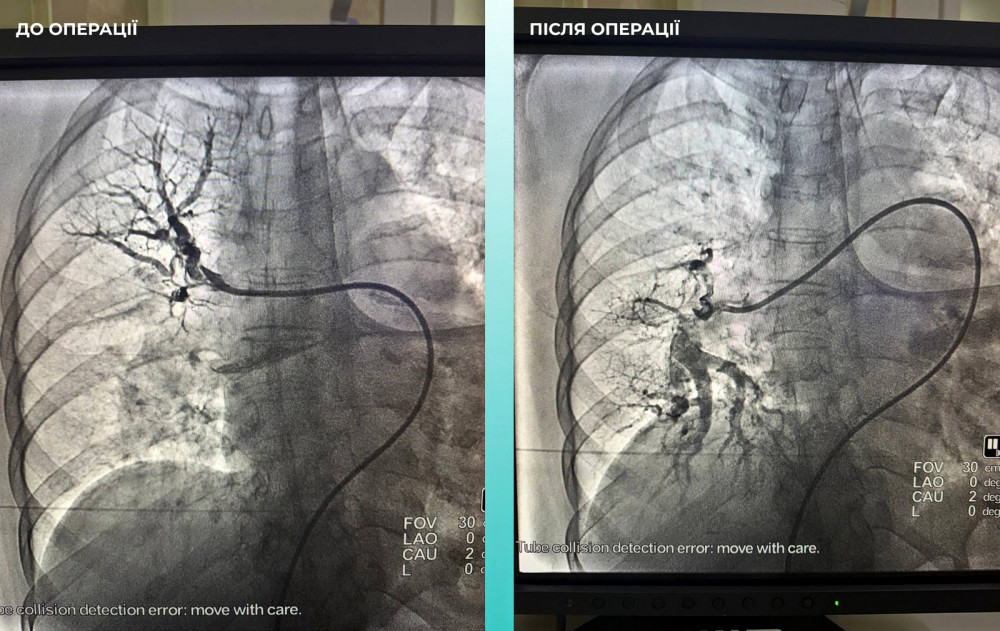

Лікарі також помітили, що жінка мала труднощі з диханням, тому провели додаткове обстеження легень. Виявилося, що у неї також тромбоемболія легеневої артерії.

Команда фахівців ухвалила складне, але надзвичайно важливе рішення — провести одночасну тромбектомію для мозкових та легеневих артерій.

Операція пройшла успішно. Зараз пацієнтка почувається значно краще: вона при свідомості та вже може рухати кінцівками.